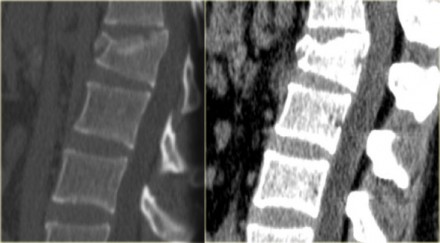

On the left images of a 31 year old male.

He was working on a roof, fell approximately 5 meters landing on his feet.

He complained of pain in left lower extremity and lower back.

First study the images, then continue reading.

On the x-ray there is a hyperflexion injury of L1 with

involvement of the anterior column and possible involvement of the

middle column.

The sagittal reconstructions of the CT demonstrate that the posterior

part of the vertebral body is of normal height, but there is some

involvement of the posterior part of the vertebral body.

There is debate on how to treat these patients and if there is any role of MRI in these cases.

If you are aggressive you could call this a two column injury, which would require stabilizing surgery.

If you are conservative you could call this an injury with only minor involvement of the middle column.

The MR images show bone marrow edema in the involved vertebral body, but no additional soft tissue injury.

Based on the fact that the MR did not show any additional findings, this patient was treated as having a single column injury.

Consultation with orthopedic surgery recommended conservative management with a TLSO brace.

Nowadays there is a tendency to treat these thoracolumbar injuries

conservatively, even if there is slight involvement of the middle

column.

The role of MRI in these cases is not clear yet.